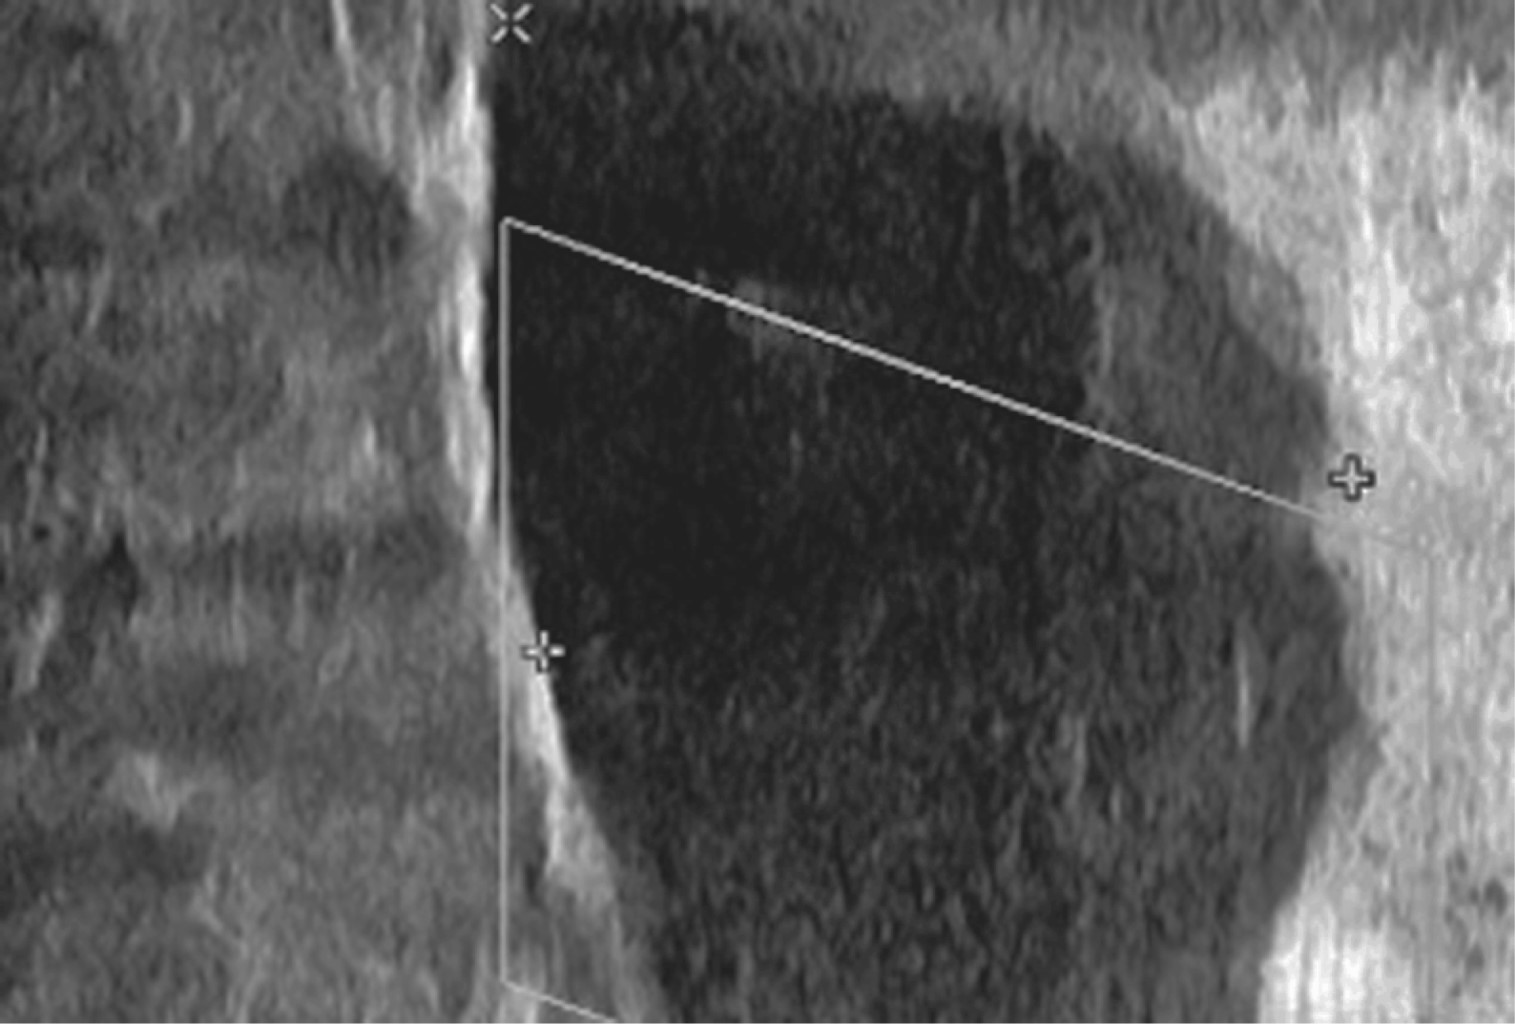

A su llegada a urgencias, se realizó un ultrasonido Doppler ante sospecha de TVP por presentar disnea de medianos que progresa a pequeños esfuerzos (Figura 1), en el cual se reporta: trombosis de la vena safena izquierda parcialmente canalizada, pantorrilla izquierda con imagen hipoecoica. Asimismo, por sospecha diagnóstica de tromboembolia pulmonar (TEP), se realizó angiotomografía axial computarizada de tórax en la que se reportó tromboembolia pulmonar segmentaria bilateral, por lo que se inició manejo con enoxaparina 60 mg subcutáneos cada 24 horas, así como furosemida 60 mg intravenosos dosis única. En la exploración física, se encontró una extremidad pélvica izquierda con aumento de volumen a nivel de rodilla y pierna hasta ambos maléolos y datos de insuficiencia venosa periférica. Dolor a la palpación sobre hueco poplíteo, línea articular medial y lateral de rodilla sin crépito óseo palpable. Arcos de movilidad de rodilla con flexión activa de 20°, flexión pasiva de 30°, limitadas por dolor sobre hueco poplíteo, línea articular medial y lateral. Fuerza de rodilla 4/5 de la escala de Daniels por dolor referido sobre hueco poplíteo, línea articular medial y lateral y debilidad. Sensibilidad conservada por dermatomas. Reflejos osteotendinosos patelar y aquíleo ++/++. Pulsos distales presentes. Llenado capilar inmediato. Se realizaron radiografías anteroposteriores con apoyo, lateral a 30° y axial a 45° de rodilla izquierda; se observa gonartrosis con presencia de disminución del espacio articular de predominio medial, esclerosis subcondral y osteofitos, además de edema de tejidos blandos (Figura 2). Se solicitaron estudios de laboratorio los cuales informaron los siguientes resultados: péptido natriurético cerebral (BNP) 128, glucosa 71, nitrógeno ureico en sangre (BUN) 16.3, creatinina 0.45, sodio 135, potasio 6.16, tiempo de protrombina (TP) 11.7, INR 1.04, dímero D 10,994, leucocitos 11.2, hemoglobina 11.1, examen general de orina: nitritos positivos, esterasa leucocitaria 250 leu/UI.

Figura 1